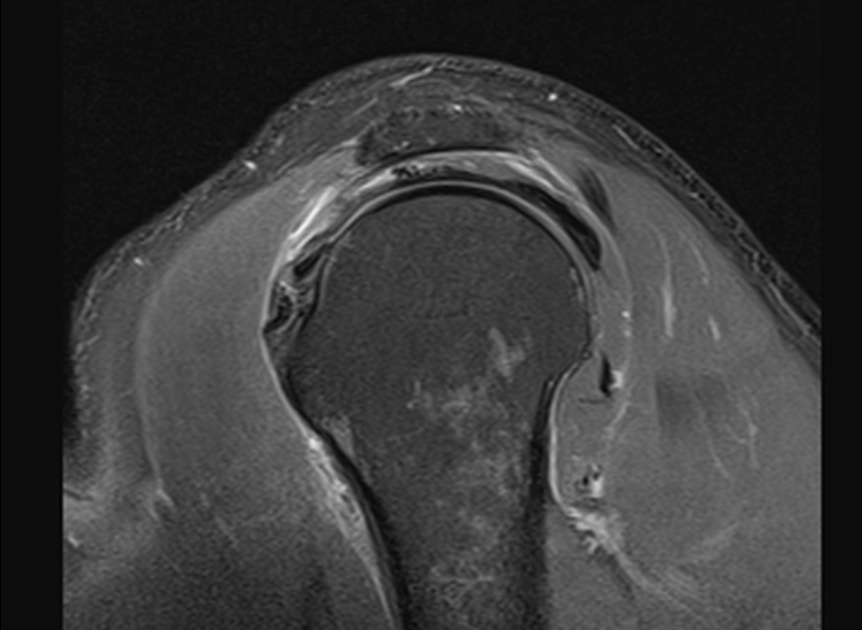

The surgeon said the tear wasnt visible from the articular side and debridement was necessary to reach it from the bursa. The tendon was stuck down and a side to side repair was necessary. You can make out the central defect in the footprint with intact articular and burial surfaces.

I have seen a few of these in Infraspinatus, as per the article linked below, but this was my first in Supraspinatus. Reference article.

Massive interstitial delamination of Supraspinatus with retraction